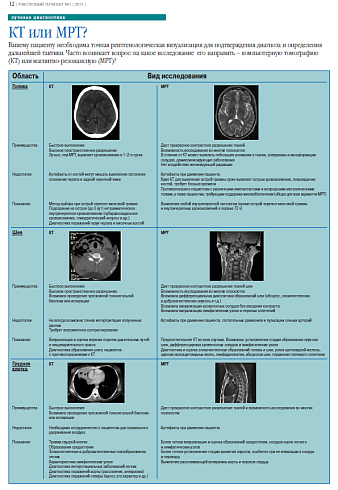

Вашему пациенту необходима точная рентгенологическая визуализация для подтверждения диагноза и определения дальнейшей тактики. Часто возникает вопрос: на какое исследование его направить – компьютерную томографию (КТ) или магнитно-резонансную (МРТ)?